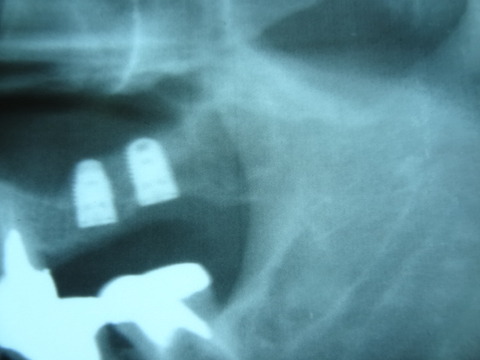

以下の写真は 先日 行ったソケットリフト症例です。

サイナスリフト症例となるべく 骨の薄い部分も存在する症例であります。

黄色の線で書いた上顎洞底の粘膜( シュナイダー膜)を破らないようにしてリフトアップさせます。

上顎骨とシュナイダー膜の間に インプラント体(フィクスチャー)と 骨補填材(将来 骨に置換され

るものです)を入れていきます。

バルーンリフトテクニックは使用しておりませんが、リフティングドリルと骨補填材の使用により、

全く患者様に負担の無い治療ができました。 治療時、治療後 共に殆ど痛みはなかった

ということでありました。